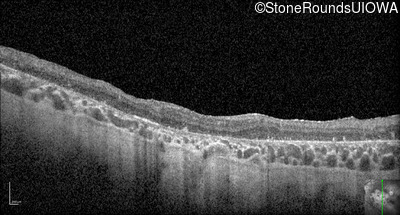

Optical Coherence Tomography - Left - 10/300

Exemplar / OCT Stack

OCT Stack